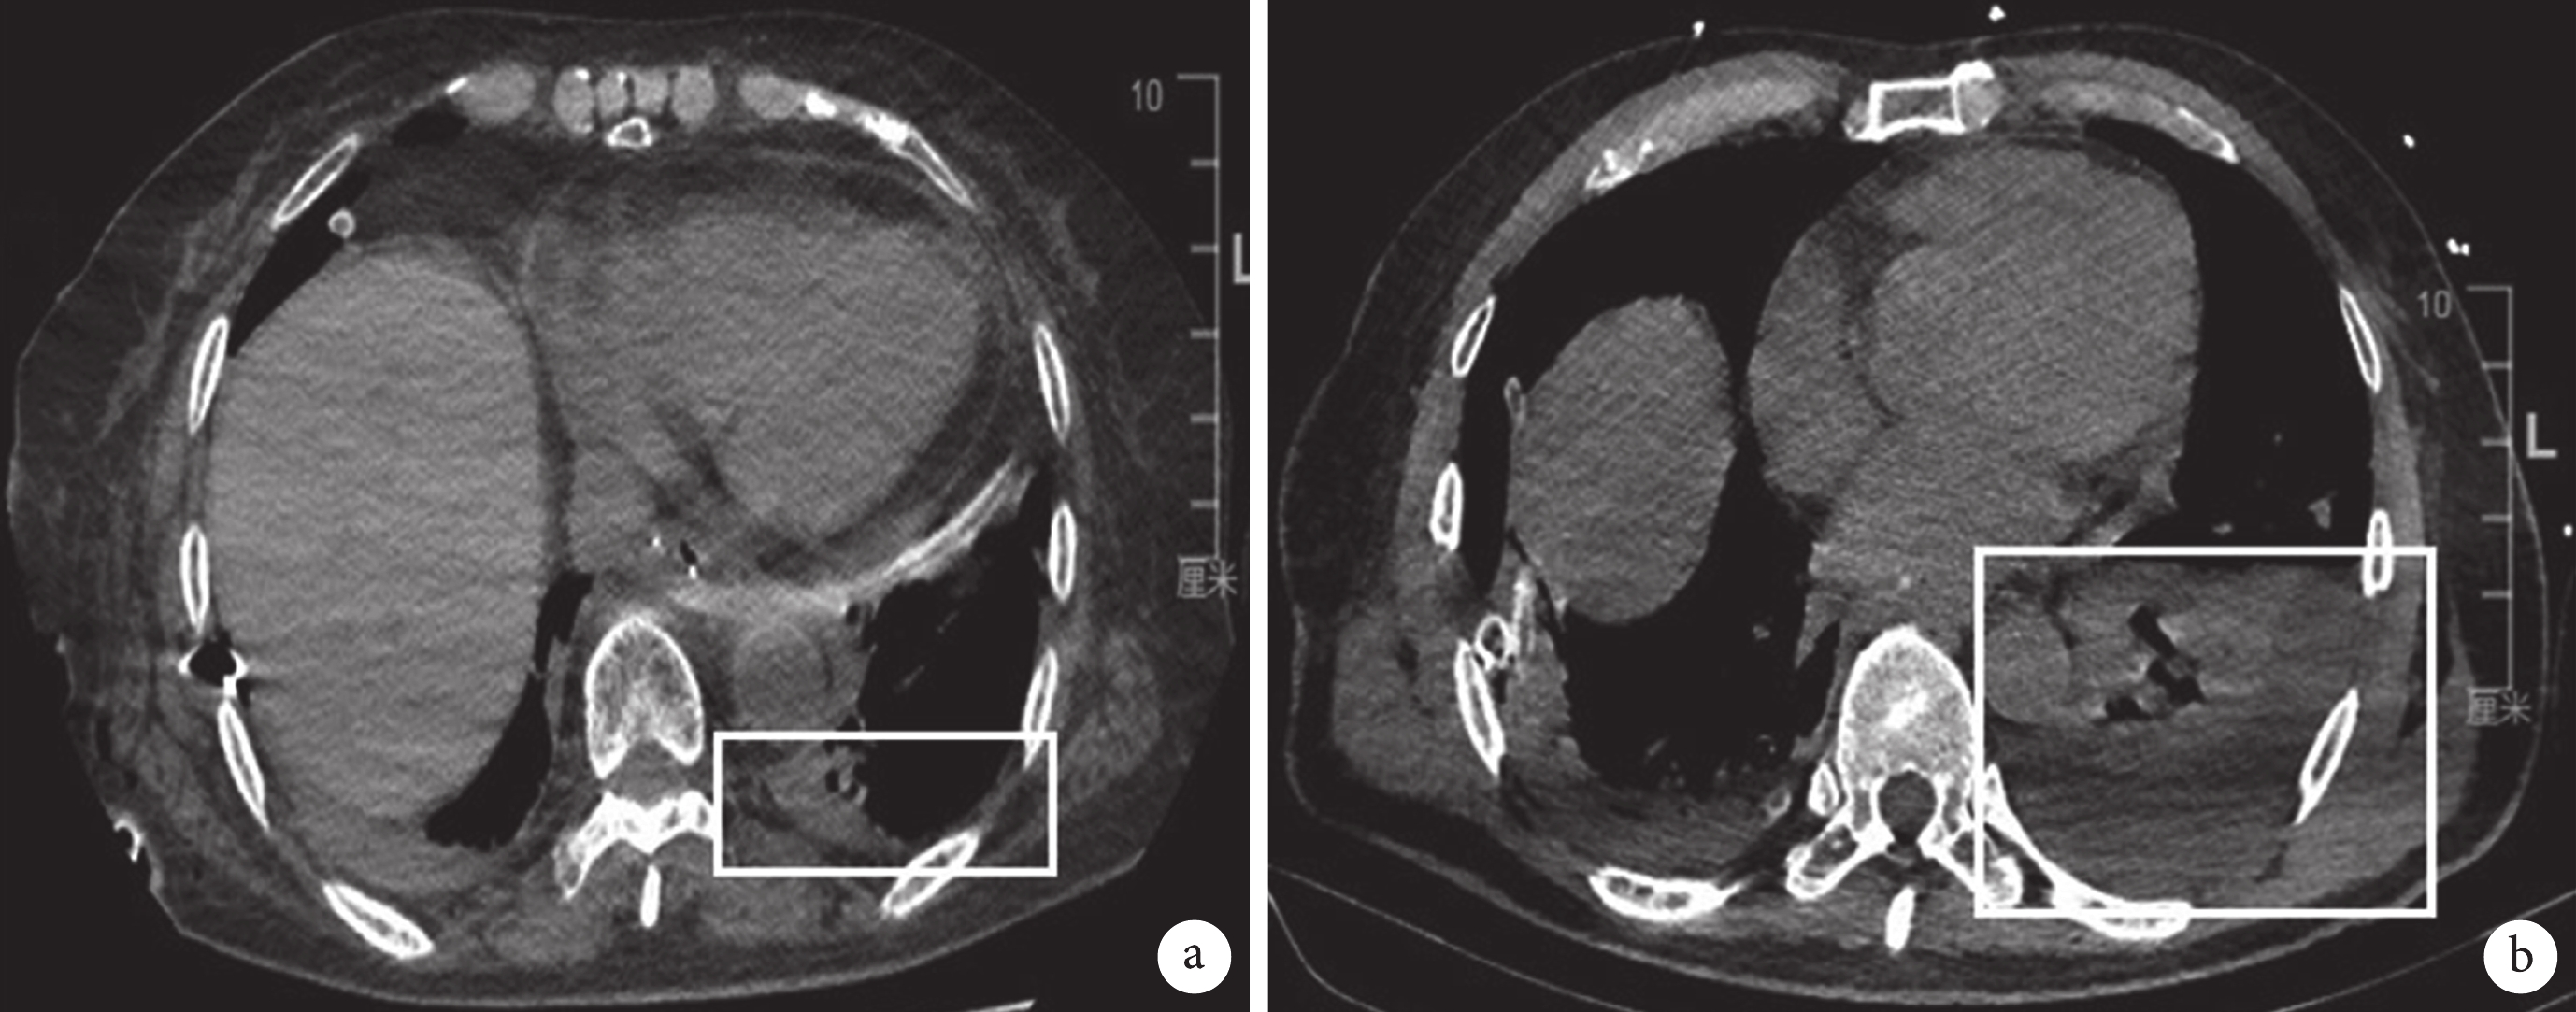

對照組采用傳統的右側胸腔引流+縱隔引流方法,術中經機器人2號臂切口(近腋后線第8肋間)放置唯朗28F一次性使用胸腔引流管 1根(廣東先來醫療器械有限公司),機器人鏡頭直視下將胸腔引流管沿后縱隔向上到達胸頂部,經助手孔切口(第7肋間)放置前端帶數個側孔的縱隔引流管(一次性負壓引流管),機器人鏡頭直視下確認縱隔引流管位于食管床的后方并且頭端置于游離的食管最上段,外接負壓引流球持續引流。觀察組:右側胸腔閉式引流管和對照組置管方法相同,縱隔引流管的側孔數目較對照組的適度增加,在機器人直視下用1號臂抓鉗將縱隔引流管頭端從左側縱隔胸膜破口逆行置入左側胸腔內,同時保留尾部數個側孔位于縱隔食管床內以進行縱隔引流,此時首先單獨膨脹左肺可見左肺復張并擠壓縱隔胸膜,然后再雙肺通氣于機器人直視下確認雙肺復張,置入縱隔及對側胸腔內的引流管仍外接負壓引流球持續引流。所有入組患者術后第3~4 d均常規安排復查胸部CT且確認胸腔引流管和縱隔引流管在位;見圖1。兩組患者的胸腔引流管拔管指征為:引流量<100 mL/d,復查胸部CT無明顯肺不張或胸腔積氣、積液后拔除胸腔引流管。縱隔引流管待患者進食后1~2 d并無明顯引流后拔除。出現術后吻合口瘺的患者待復查胸部CT及上消化道碘水造影確定吻合口完全愈合、無明顯胸腔積液后拔除胸腔引流管和縱隔引流管。

a:觀察組縱隔引流管放置入左側胸腔內(白色方框處);b:對照組縱隔引流管放置在縱隔食管床內(白色方框處)